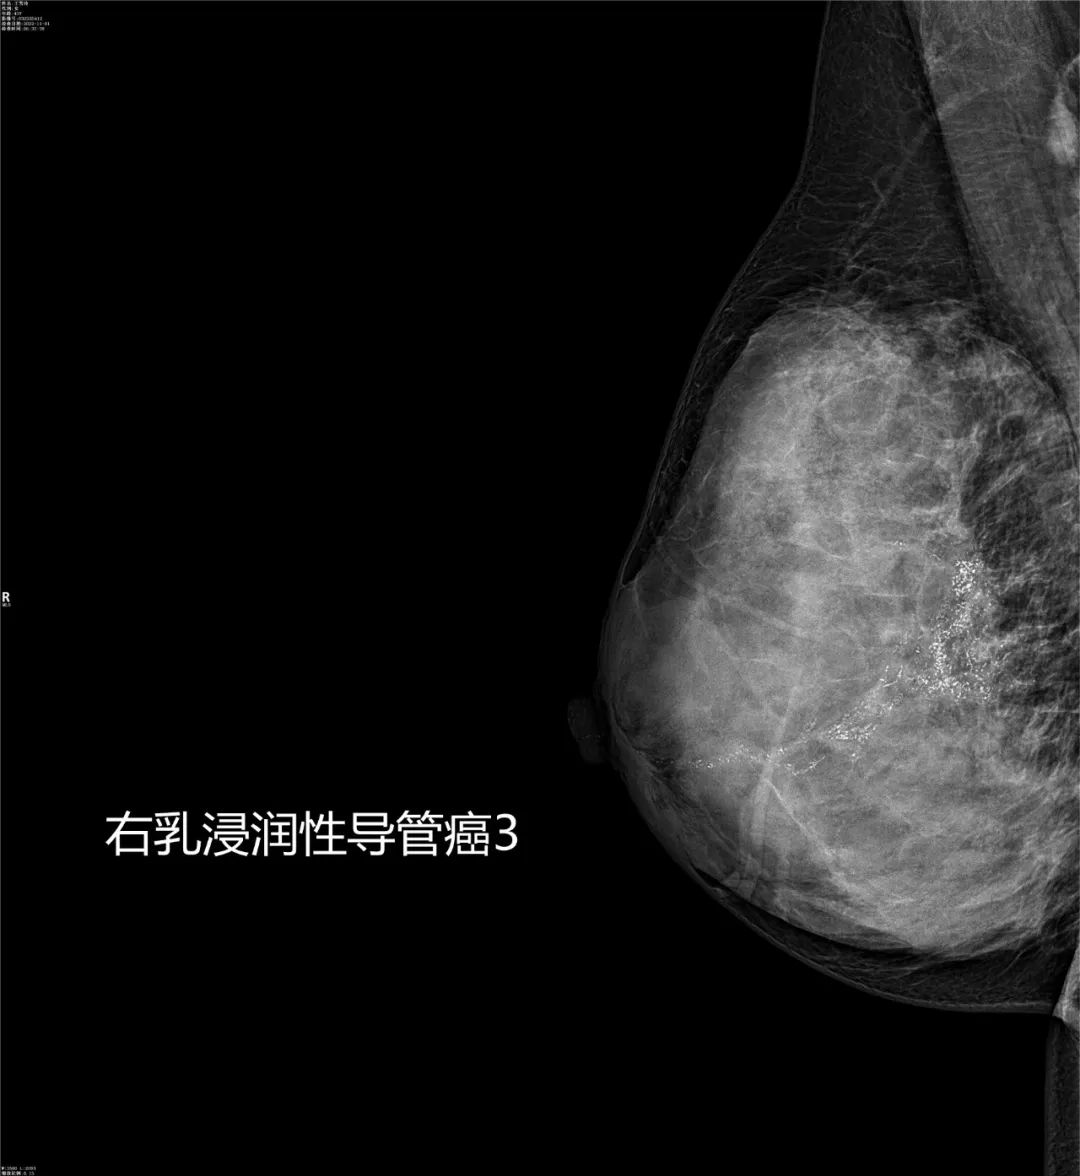

乳腺疾病的诊断与体检筛查